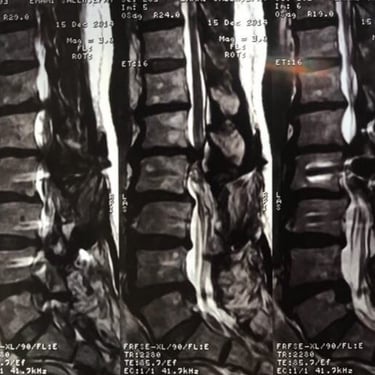

Adjacent level L1-L2 and L4-L5 disc herniations (5 years after a complicated lumbar fixation surgery) treated by Discogel Injection